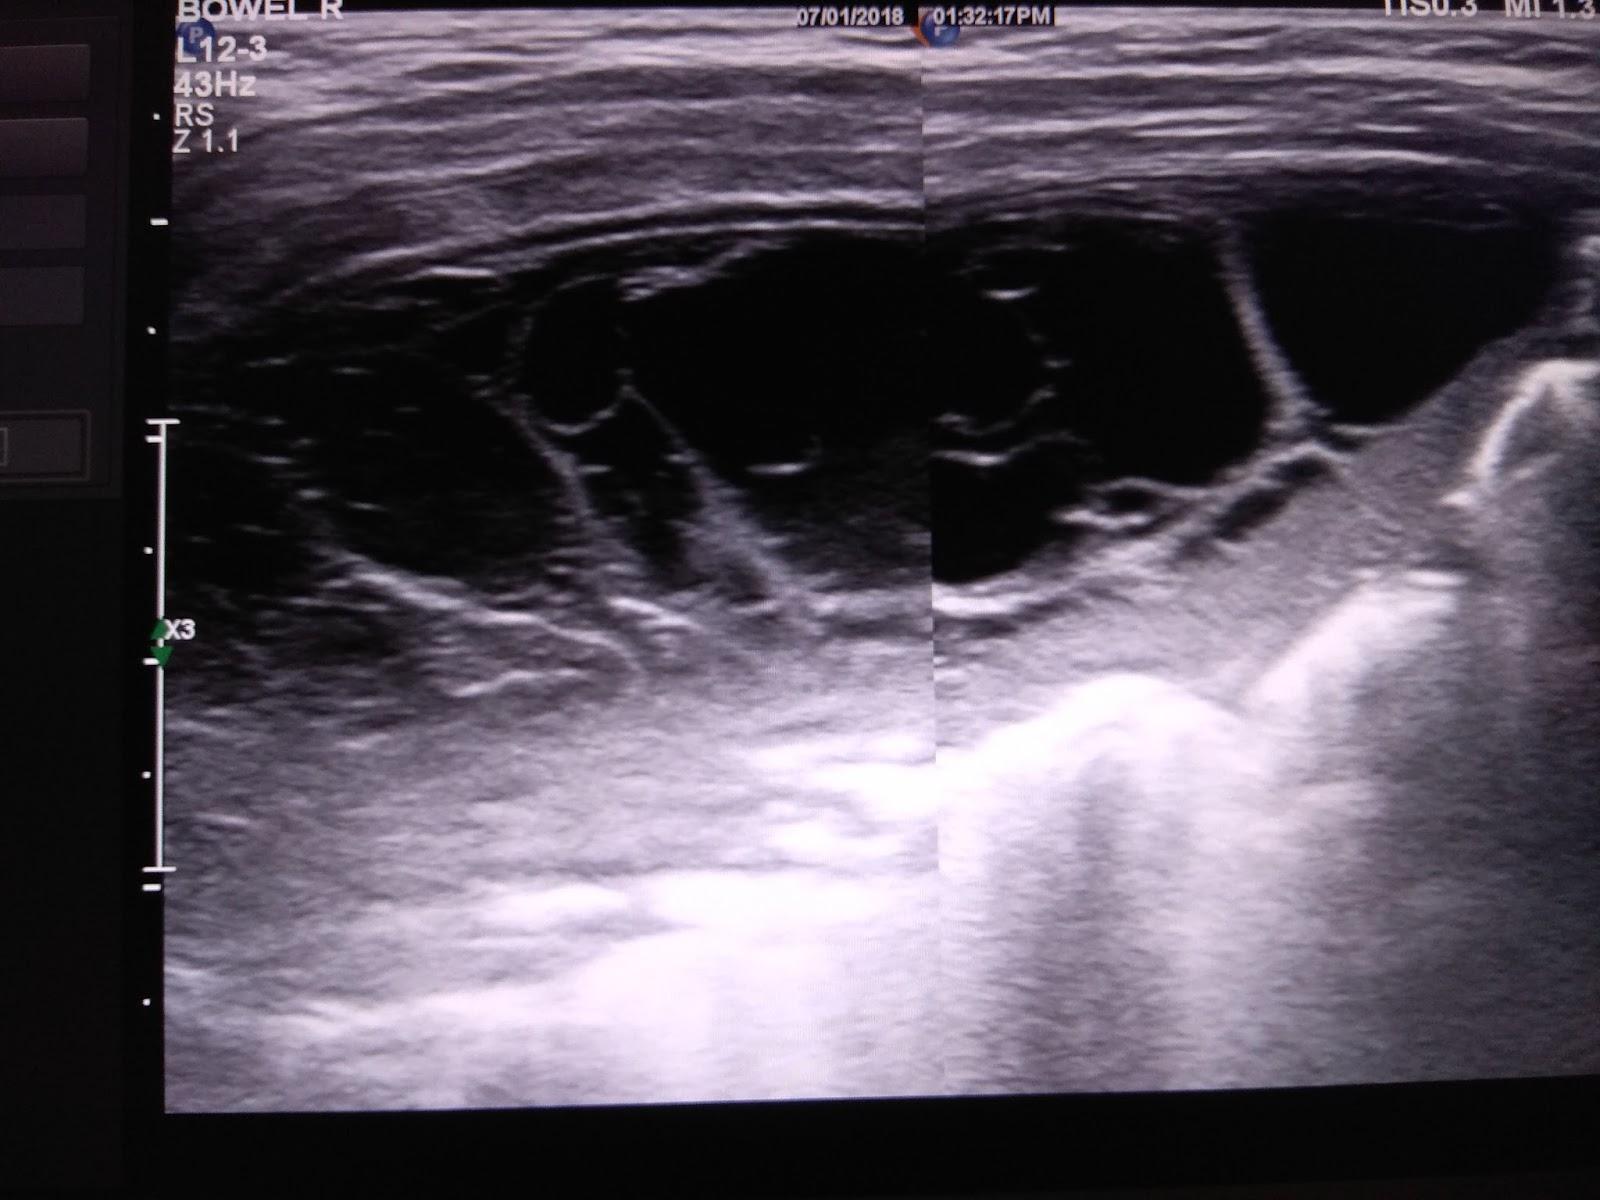

Examples of PE on the chest ultrasound. Anechoic space represents fluid... Download Scientific What Is A Chest Ultrasound A chest ultrasound is an imaging test that uses sound waves to look at the structures and organs in your chest. The thoracic anatomy is composed of the chest wall that is made of musculature including intercostal muscles and pectoralis. A chest ultrasound is an imaging test. It can help your healthcare. What is a chest ultrasound? It uses sound. What Is A Chest Ultrasound.